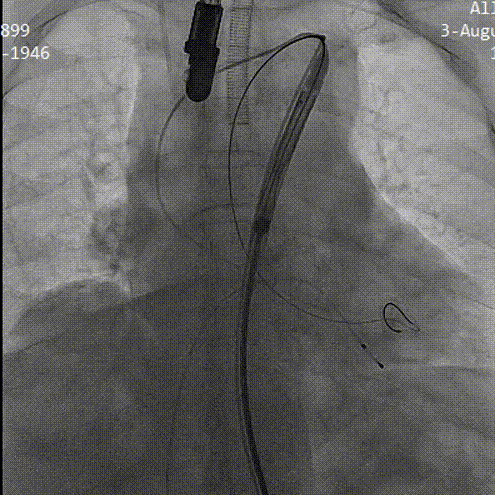

术中影像

导丝顺利跨瓣

TaurusAtlas 20mm球囊充分预扩张,无明显腰征 无漏

TaurusElite输送器顺利过弓